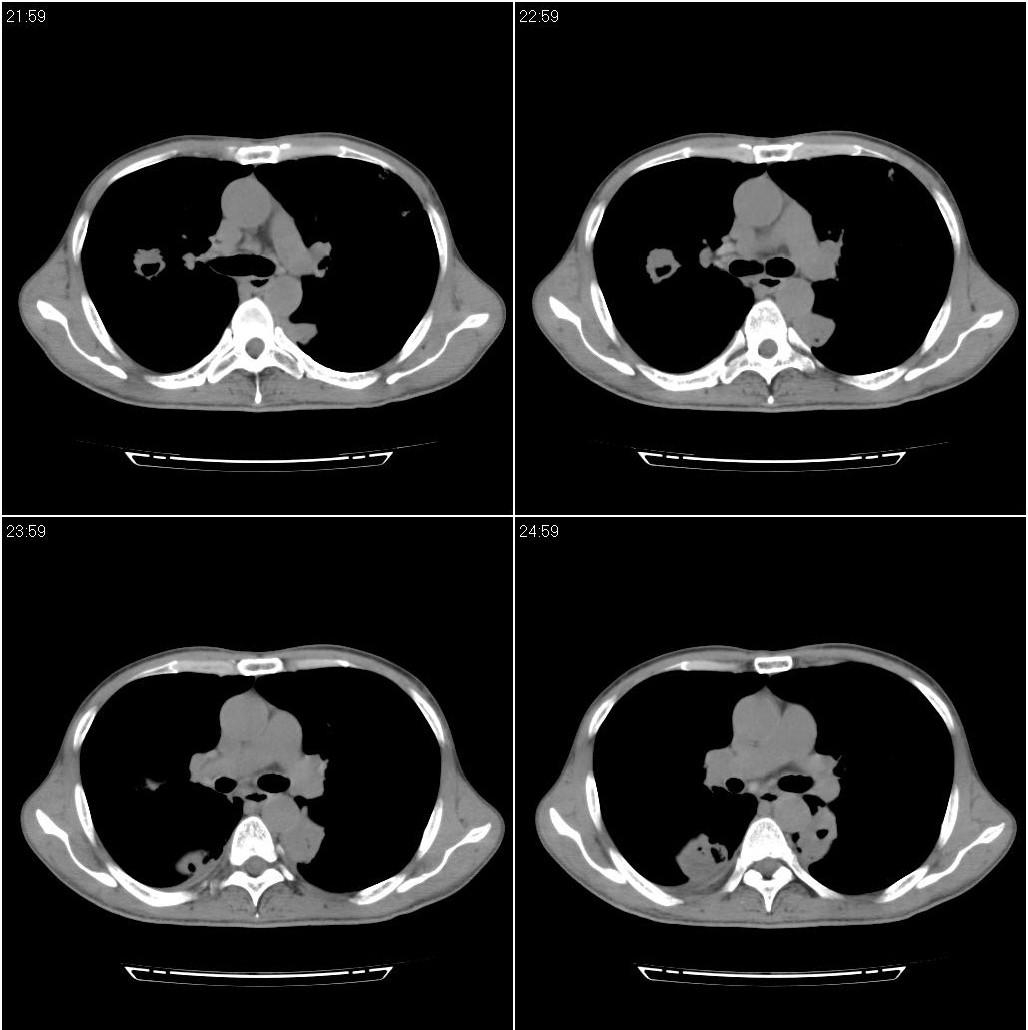

标题: CT23980:男性,47岁。近来咳痰、咳血,血沉增快(40左右),

男性,47岁。近来咳痰、咳血,血沉增快(40左右),痰中未检出结核杆菌。

双肺继发性肺结核

两肺继发性肺结核并多发性结核球形成,部分病灶内空洞形成。